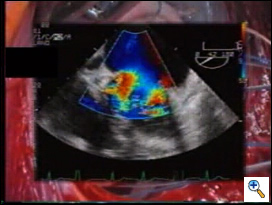

The best application of the edge-to-edge is when the valve is severely affected by myxomatous changes, with leaflet thickening, bileaflet significant prolapse and redundancy, multiple jets at Colour-Doppler TEE.

Intraoperative, post-repair TEE is mandatory, as with any other repair technique, to verify the results of the correction. In the specific setting of the edge-to-edge technique, TEE should exclude not only residual regurgitation, but also valve stenosis. Valve area may be assessed by Doppler methods, since flow velocity through the valve is not affected by the type of surgical procedure.4 We mostly rely on planimetric valve area, assessed in the transgastric, short-axis view of the mitral valve. In case of doubts, pressure measurements of the transvalvular gradients may be obtained to exclude mitral stenosis intraoperatively. Mid-term follow-up TEE data showed good results of the repair, with stable competence and no progression of valve stenosis (see chart3). Exercise Doppler-echocardiography may be useful in case of suspicion of mitral stenosis at baseline examination. It must be noted that following double orifice repair, valve area is flow dependent (functional reserve), since it increases during exercise, as for the native mitral valve.5